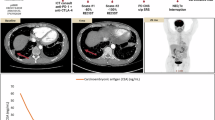

As of December 2024, the median follow-up period was 13.3 months. The median PFS was 7.8 months, and the median OS was 28.8 months (Fig. 1). Based on RECIST version 1.1, the ORR was 17.2%, and the DCR was 79.3%. Among them, 5 patients achieved PR, 18 patients SD, and 6 patients experienced PD. The best percent change in the target lesion diameter from baseline for all 25 patients is shown in Fig. 2A. Six patients were still receiving maintenance therapy at the data cut-off day (Fig. 2B). The median PFS was 6.77 months (95% CI 2.87–10.5) in patients with liver metastasis and 14.7 months (6.9–NA) in patients with non-liver metastasis (HR 3.684, log-rank test P = 0.0118, Fig. 3A). The median PFS was 8.03 months (95% CI 5.7–NA) in patients with lung metastasis and 6.9 months (4.17–NA) in patients with non-lung metastasis (HR 0.6865, log-rank test P = 0.387, Fig. 3B).